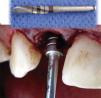

Extracción de la corona del OD 12 mediante periostótomos y el resto radicular con instrumentos rotatorios (Fresa espiral ACT3015, 3i®) (Figura 4).

Inserción del implante 3i®, Osseotite Certain Micro Miniimplant de diámetro 3.25 y 15mm de longitud (Figura 7).